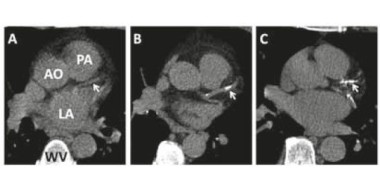

Het diagnostische arsenaal wordt groter. Het aantal sneltesten neemt toe (CRP, cholesterol, troponine, D-dimeer). Maar zijn ze betrouwbaar, wanneer zetten we ze in en wanneer is dat juist niet zinvol? Ook kan de huisarts meer MRI-, CT-, laboratorium- en functieonderzoek aanvragen. Gaan we met de tijd mee, kunnen we het allemaal verwerken en interpreteren, of is er sprake van overdiagnostiek? Wanneer gaat meerwaarde over in meer twijfel?